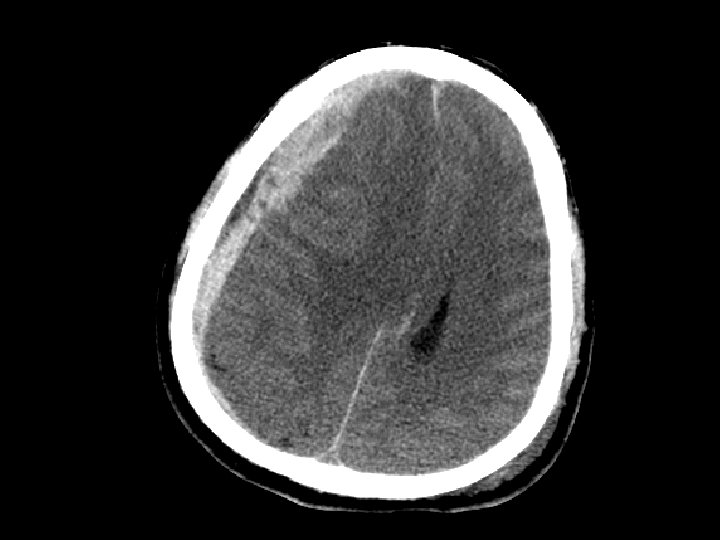

Máu tụ ngoài màng cứng (EDH) • Chảy máu ngoài màng cứng – Thường do động mạch (động mạch màng não giữa) nhưng cũng có thể do chảy máu tĩnh mạch • CT: hình tụ máu thấu kính lồi – Xuất huyết nằm khư trú do hạn chế trong khoảng giữa màng cứng và sọ • 5 -15% bệnh nhân CTSN có tụ máu ngoài màng cứng

Máu tụ ngoài màng cứng • Có nguy cơ tăng khối choán chỗ và gây thoát vị liềm não (giãn đồng tử) – “khoảng tỉnh và sau đó tử vong” • Quan sát được tụ máu ngoài màng cứng • Tụ máu ngoài màng cứng gây choán chỗ cần can thiệp phẫu thuật